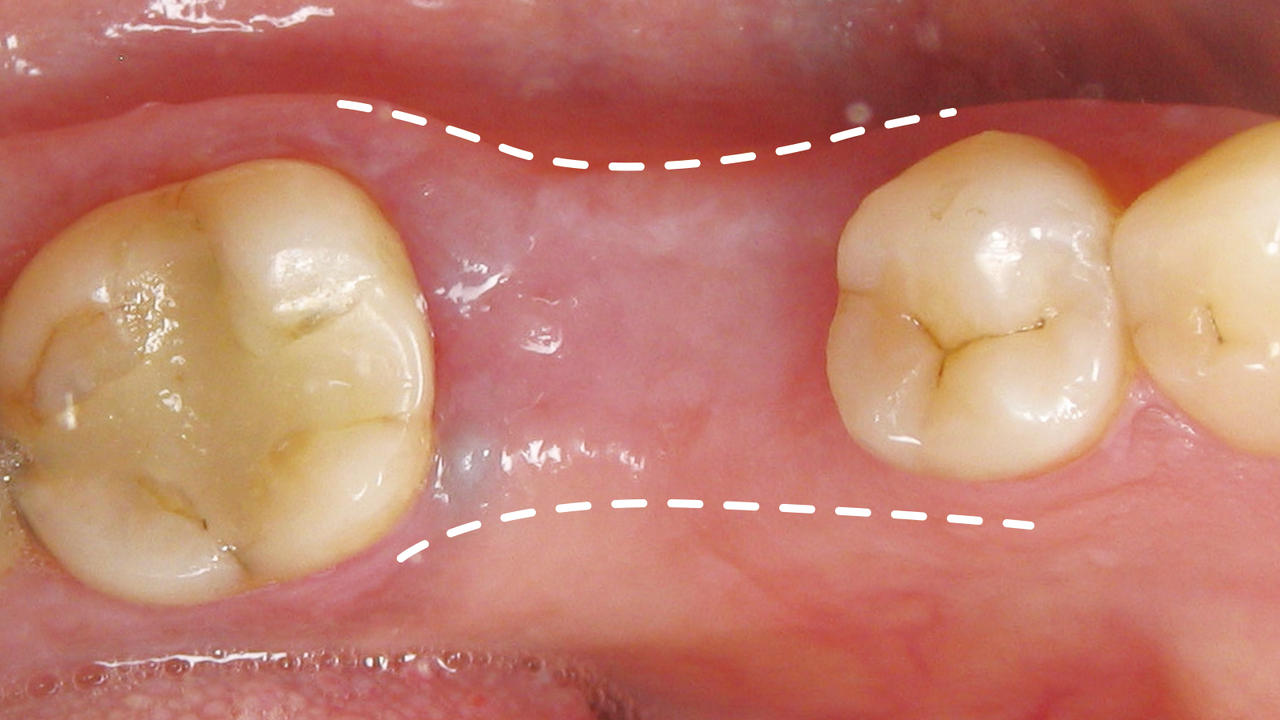

발치 후 시간 경과에 따른 잇몸뼈의 두께 변화

뼈이식 양이 많은 경우

뼈이식술 3-6개월 후 임플란트 식립

뼈이식 양이 적은 경우

뼈이식과 동시에 임플란트 식립

잇몸뼈가 부족해도

임플란트 할 수 있나요?

잇몸의 폭이 좁으면 안정적인 임플란트 식립이 어려워

잇몸뼈를 쪼갠 후 공간을 넓히는 수술을 합니다.

잇몸뼈가 부족해도 임플란트 할 수 있나요?

잇몸의 폭이 좁아지면 안정적인 임플란트 식립이 어려우므로

잇몸뼈를 쪼갠 후 공간을 넓히는 릿지 스플릿 수술을 진행하게 됩니다.

릿지 스플릿 진행 단계